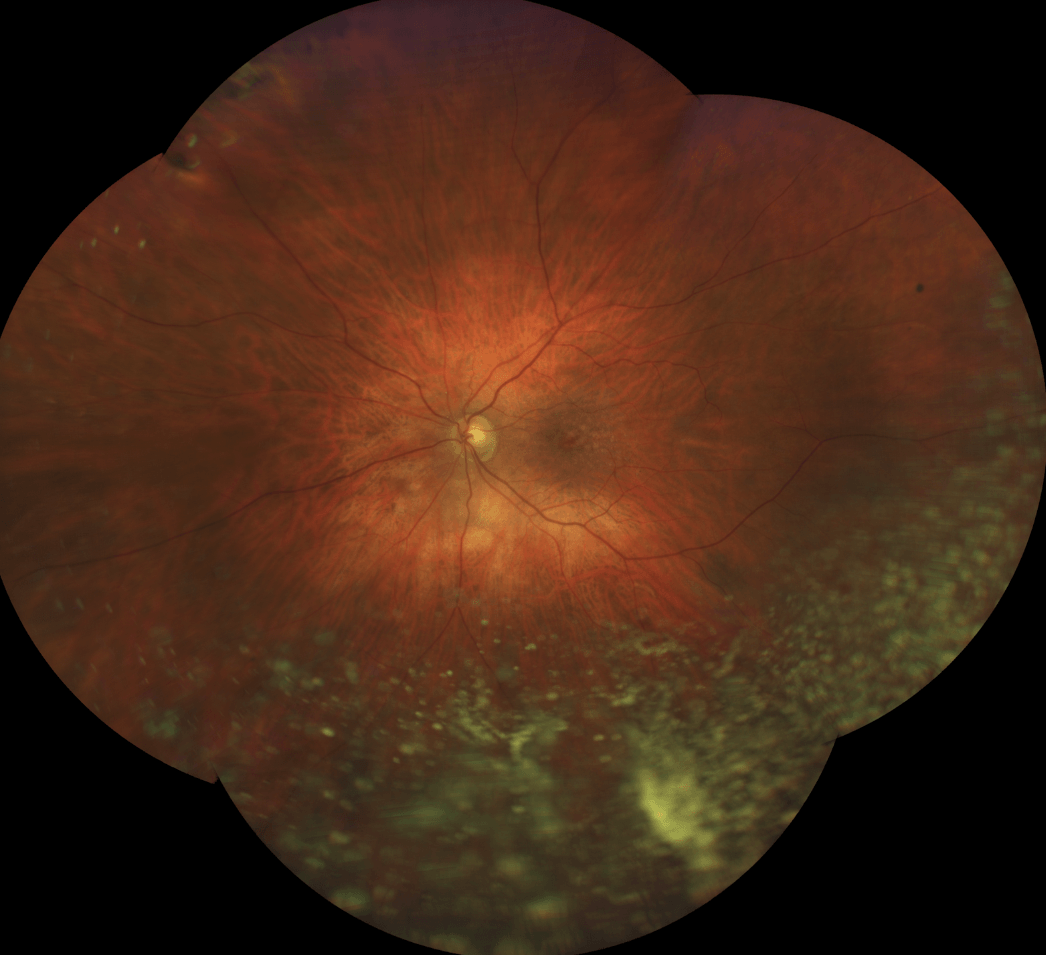

The dense material (and vitreous cells) in this UWF image should not be confused with routine floaters, because this material is consistent with a life-threatening condition.

What is Primary Intraocular Lymphoma?